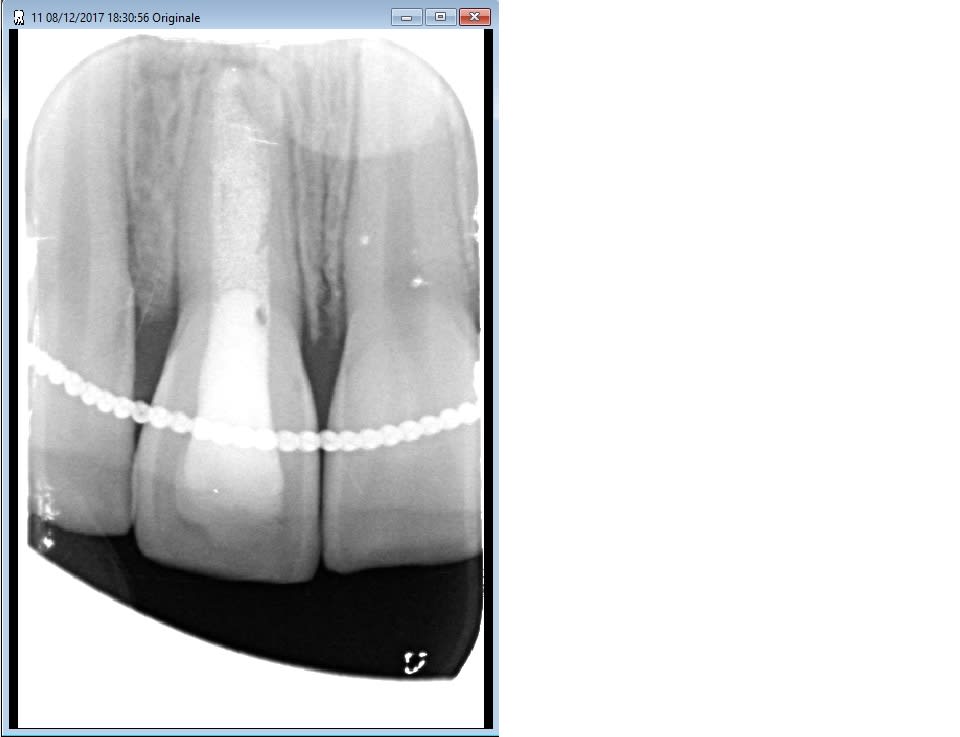

Bonjour et meilleurs voeux à tous, j'ai réalisé en 2013 une apexification avec un bouchon de mta chez ma jeune patiente suite à nécrose et fistule. Tout a très bien évolué et je pense que la dent est sauvée mais désormais on se retrouve avec une dent très grisonnante. Ma question est de savoir si on peut tenter un éclaircissement interne au perborate sur ce type de dyschromie. Je vous joint une radio au cas où, je n'ai pas pensé à prendre une photo!!! Merci pour votre retour